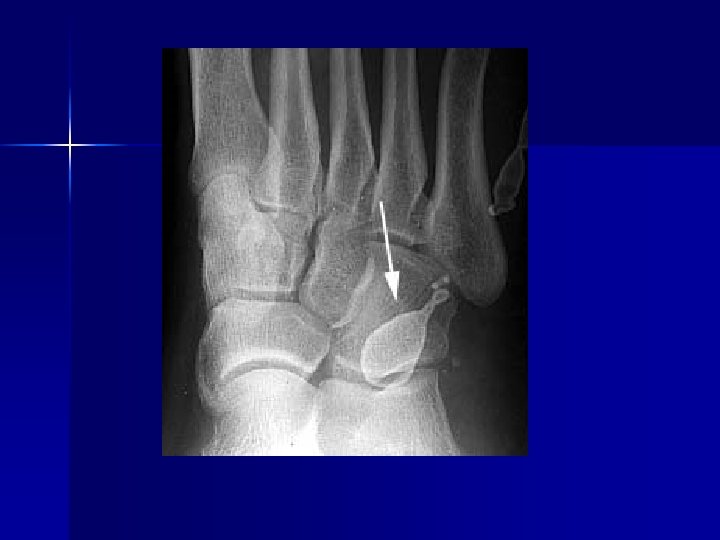

Name & cause of this?

Evaluating Images What do you think?

n n n Does this show good detail? Is all of the anatomy present? How is the density / contrast?